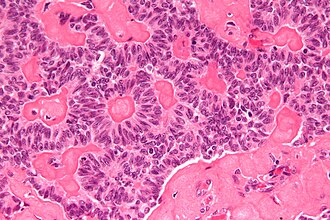

'''Sex cord-stromal tumours''' are a group of tumours found in the [[testis]] and [[ovary]] that arise from the cells that support the germ cells. | [[Image:Sex_cord_tumour_with_annular_tubules_-_2_-_very_high_mag.jpg|thumb|right|[[Sex cord tumour with annular tubules]] (SCTAT), a type of sex cord stromal tumour. [[H&E stain]].]] | ||

'''Sex cord-stromal tumours''' (abbreviated '''SCSTs''') are a group of tumours found in the [[testis]] and [[ovary]] that arise from the cells that support the germ cells. | |||

*[[Sex cord tumour with annular tubules]] (SCTAT). | *[[Sex cord tumour with annular tubules]] (SCTAT). | ||